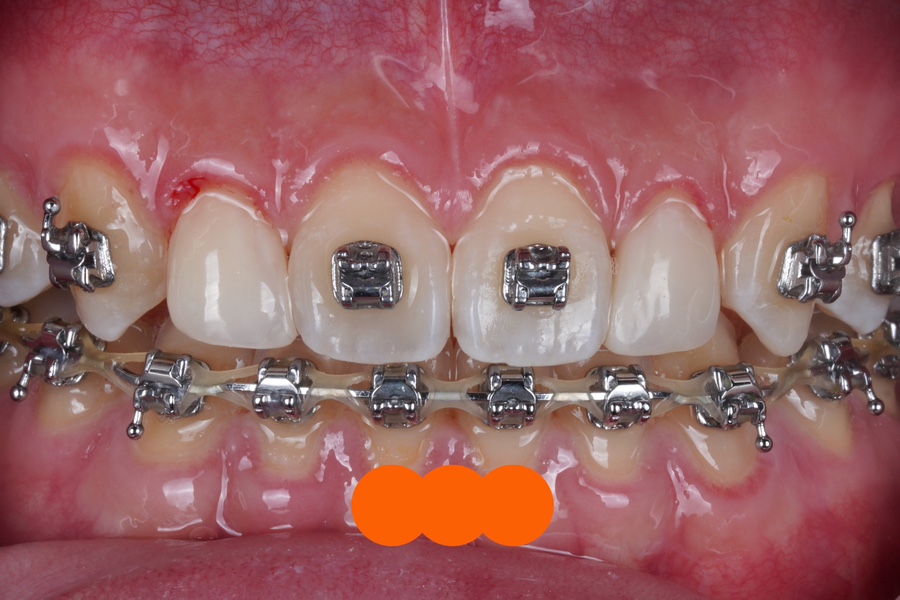

처음 오셨을 때 사진

위에 올려둔 사진은

한달 전 사진입니다.

교정 마무리 중에 오셔서

진단을 먼저 받고 가셨어요.

왜소치만 교정기 뗀 사진

교정기를 왜소치 부분만 떼고

철사를 뺀 상태에서 오셨습니다.

이렇게 와주시면 참 좋아요.

교정기를 떼니까 왜소치가 눈에 띄죠?